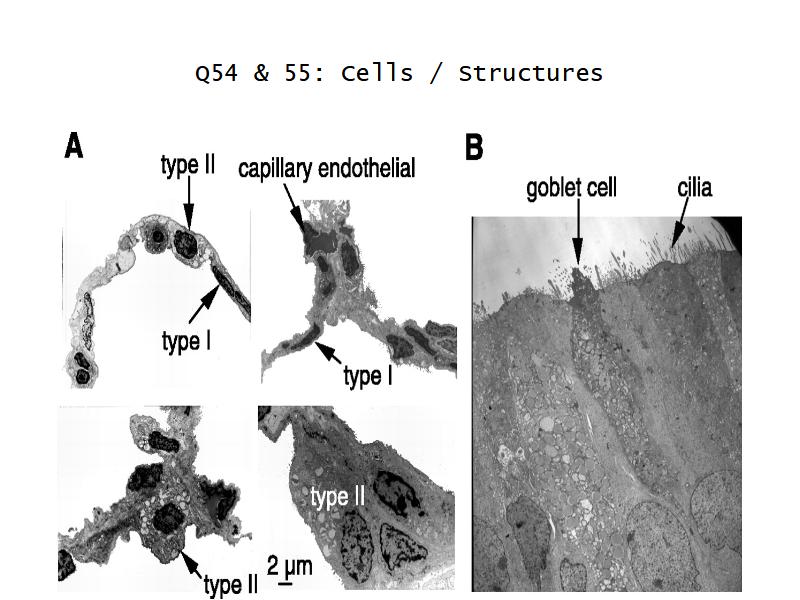

What cells are present?

Components of the Blood-Air Barrier?

Barriers

- Blood-air